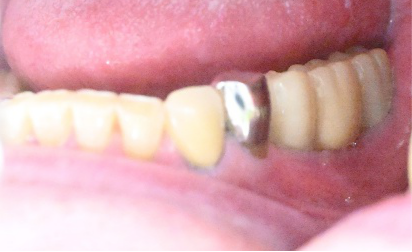

After